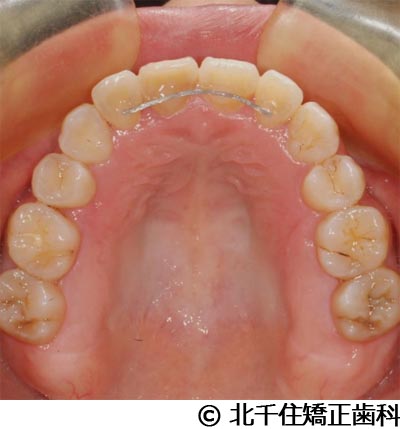

【症例3】叢生

- 治療前

- 治療後

- 治療名

- 叢生

- 費用

- 1,125,000円(税込)

- 期間

- 2年1ヵ月

- 治療回数

- 26回

- 通院頻度

- 1ヵ月ごと

- 年齢・性別

- 19歳3ヵ月・女性(初診時)

治療内容

-

患者様の症状

主訴:デコボコ、口元の突出

治療方法

上下顎第一小臼歯4本を抜歯してワイヤー矯正(セラミックブラケット)。

治療結果

叢生に対し抜歯を併用した矯正治療により、歯列および咬合関係の調整を行った症例である。治療後は保定装置を使用し、歯列および咬合の安定維持を目的として定期的な経過観察を行っている。

※治療結果は個人差があります。

治療を行う上での注意点(リスク・副作用)

歯磨き不良に伴うカリエスや歯周病、歯根吸収など。